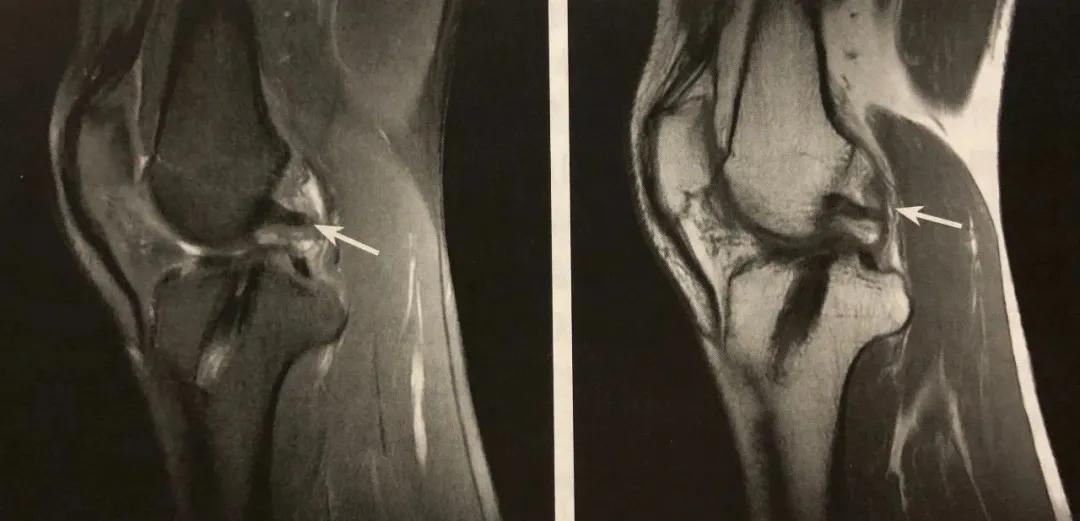

髁间窝碎片征

A、B:T1WI 冠状位、矢状位示髁间窝内小片状低信号半月板碎片;

C、D: PDWI 压脂序列冠状位、矢状位示锞间窝半月板呈低信号,其内小灶高信号。

在 MRI 脂肪抑制序列上观察最佳,冠状位或矢状位均可,表现为股骨髁间窝内除前后韧带外,见到条状或团块状低信号。

阅片要点:

1. 半月板桶柄状撕裂的间接征象;诊断敏感性不高,特异性较高;

2. 在 MRI 脂肪序列上观察最佳,冠状位或矢状位均可;冠状位最佳,注意区分前、后交叉韧带结构;

3. MRI 注意观察伴发的前、后交叉韧带损伤。